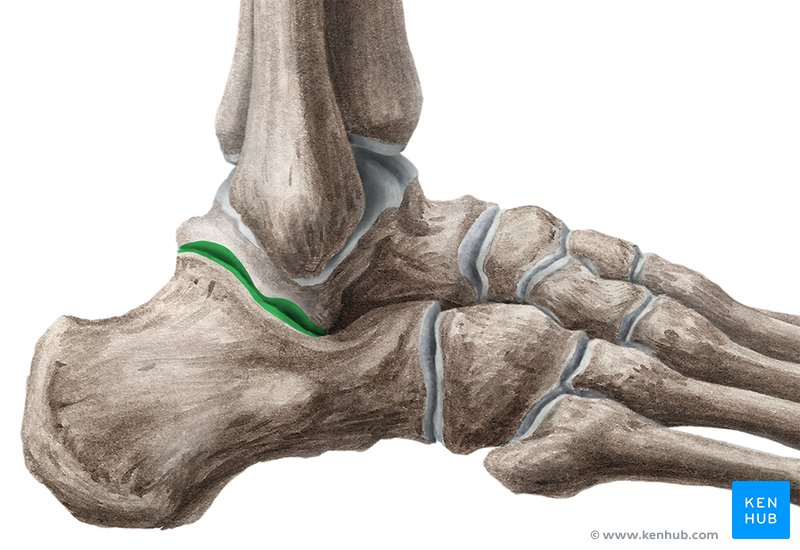

what is the sustentaculum tali?

shelf of calcaneus where tali sits on

what is the subtalar joint?

below talis

what are the 3 articulations of the subtalar joint?

anterior

middle

posterior

what are the motions of the subtalar joint?

inversion

eversion

rotation

what is the sinus tarsi?

small bony cancel that separates anterior to posterior articulations

when we sprain our ankle, where does the swelling go?

sinus tarsi

what are the ligaments of the subtalar joint?

interosseous ligament

cervical ligament

what does the interosseous ligament of the subtalar joint do?

end range inversion

what does the cervical ligament of the subtalar joint do?

end range eversion